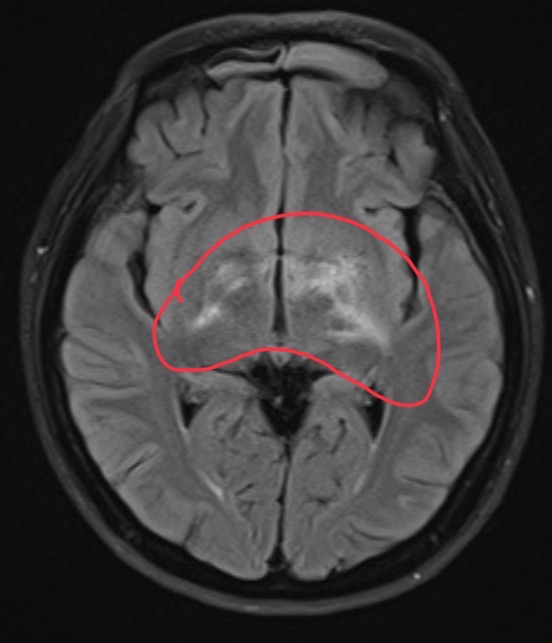

55 year-old female developed patchy vision with white specks seen bilaterally for a few weeks. Currently reports loss of vision in both eyes. There is hyper intensity around the bilateral hypothalamus, left globes pallidus, left post internal capsule, b/l optic tracts, left incision, right midbrain.

MS